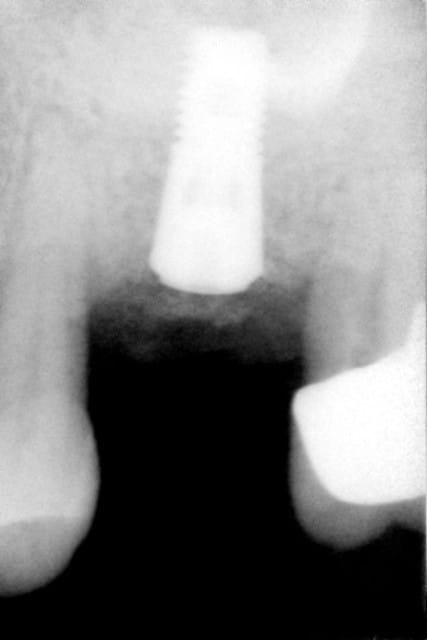

fracture plancher de 16